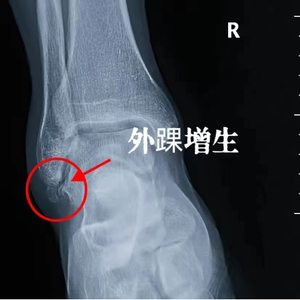

经过查体我们进行了x线检查,他的外踝有明确的骨质增生,关节间隙发生了狭窄。在侧位上谢医生做了红色的圆圈标记,这是一个非常严重的增生,仿佛在胫骨的远端长出了一个菜花,那这个增生的部位就会导致患者出现蹲起时踝关节的疼痛,它不可能是几年的时间形成的,需要的时间很漫长。